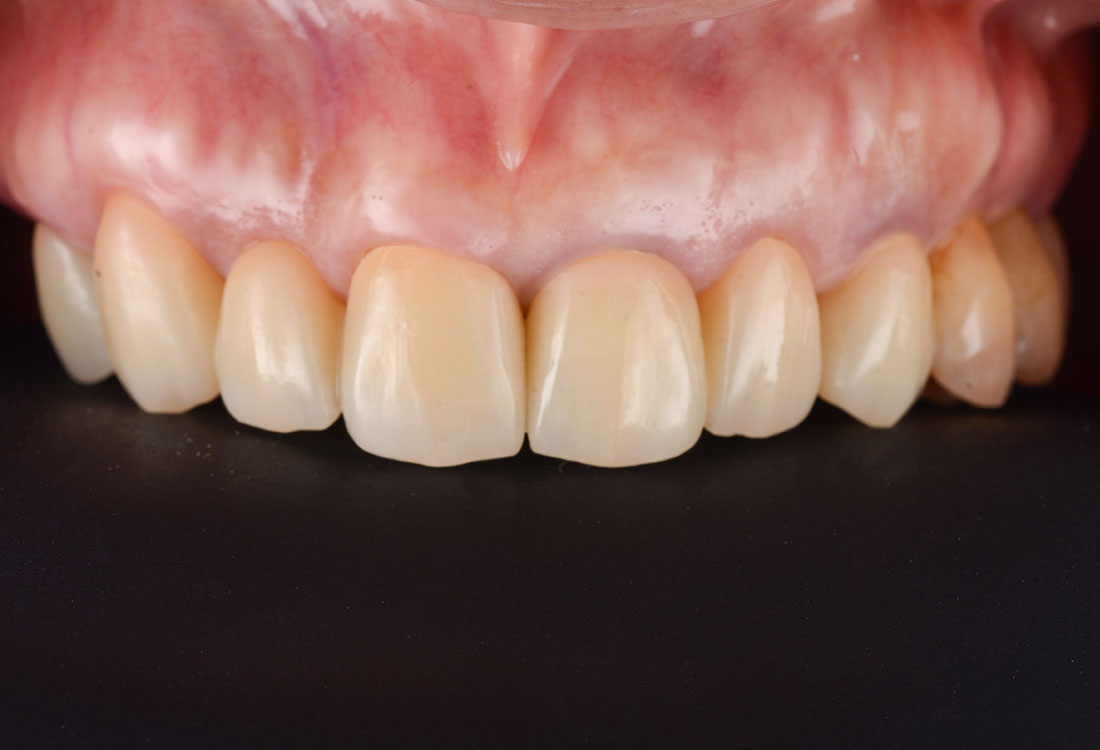

治療後

白く明るい口元になりました。